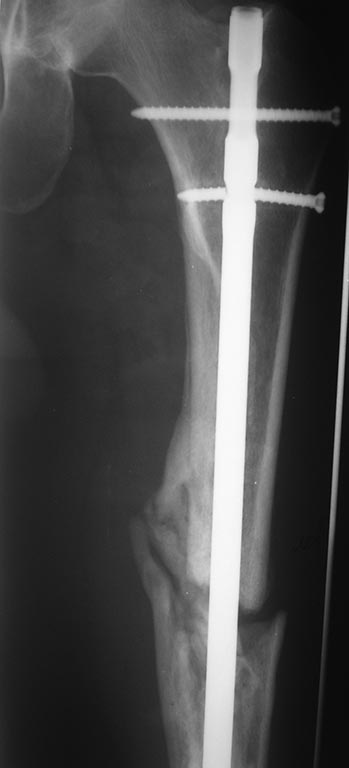

Добрый день уважаемые коллеги. Вашему вниманию представляю

пациента(мужчина, 30 лет).

Тяжелая сочетанная травма 7 мес. назад. Из скелетной травмы: открытый

перелом бедра, открытый перелом дистального метаэпифиза левого плеча,

закрытый перелом шейки левого плеча). Все повреждения были

прооперированы.Бедро синтезировано штифтом Остеомед d-11мм.

Раны зажили первично. Пациент после выписки впервые появился на

контрольный осмотр ч/з 7 месяцев. Жалобы на боли в левом бедре при

нагрузке, ощущение подвижности в месте перелома.

Передвигается без дополнительных средств опоры. Локально: отека левого

бедра нет, п/операционные рубцы без признаков воспаления. движения в

суставах левой н/конечности в полном объеме, безболезненны.( все снимки,

первичные, после операции и на сегодня